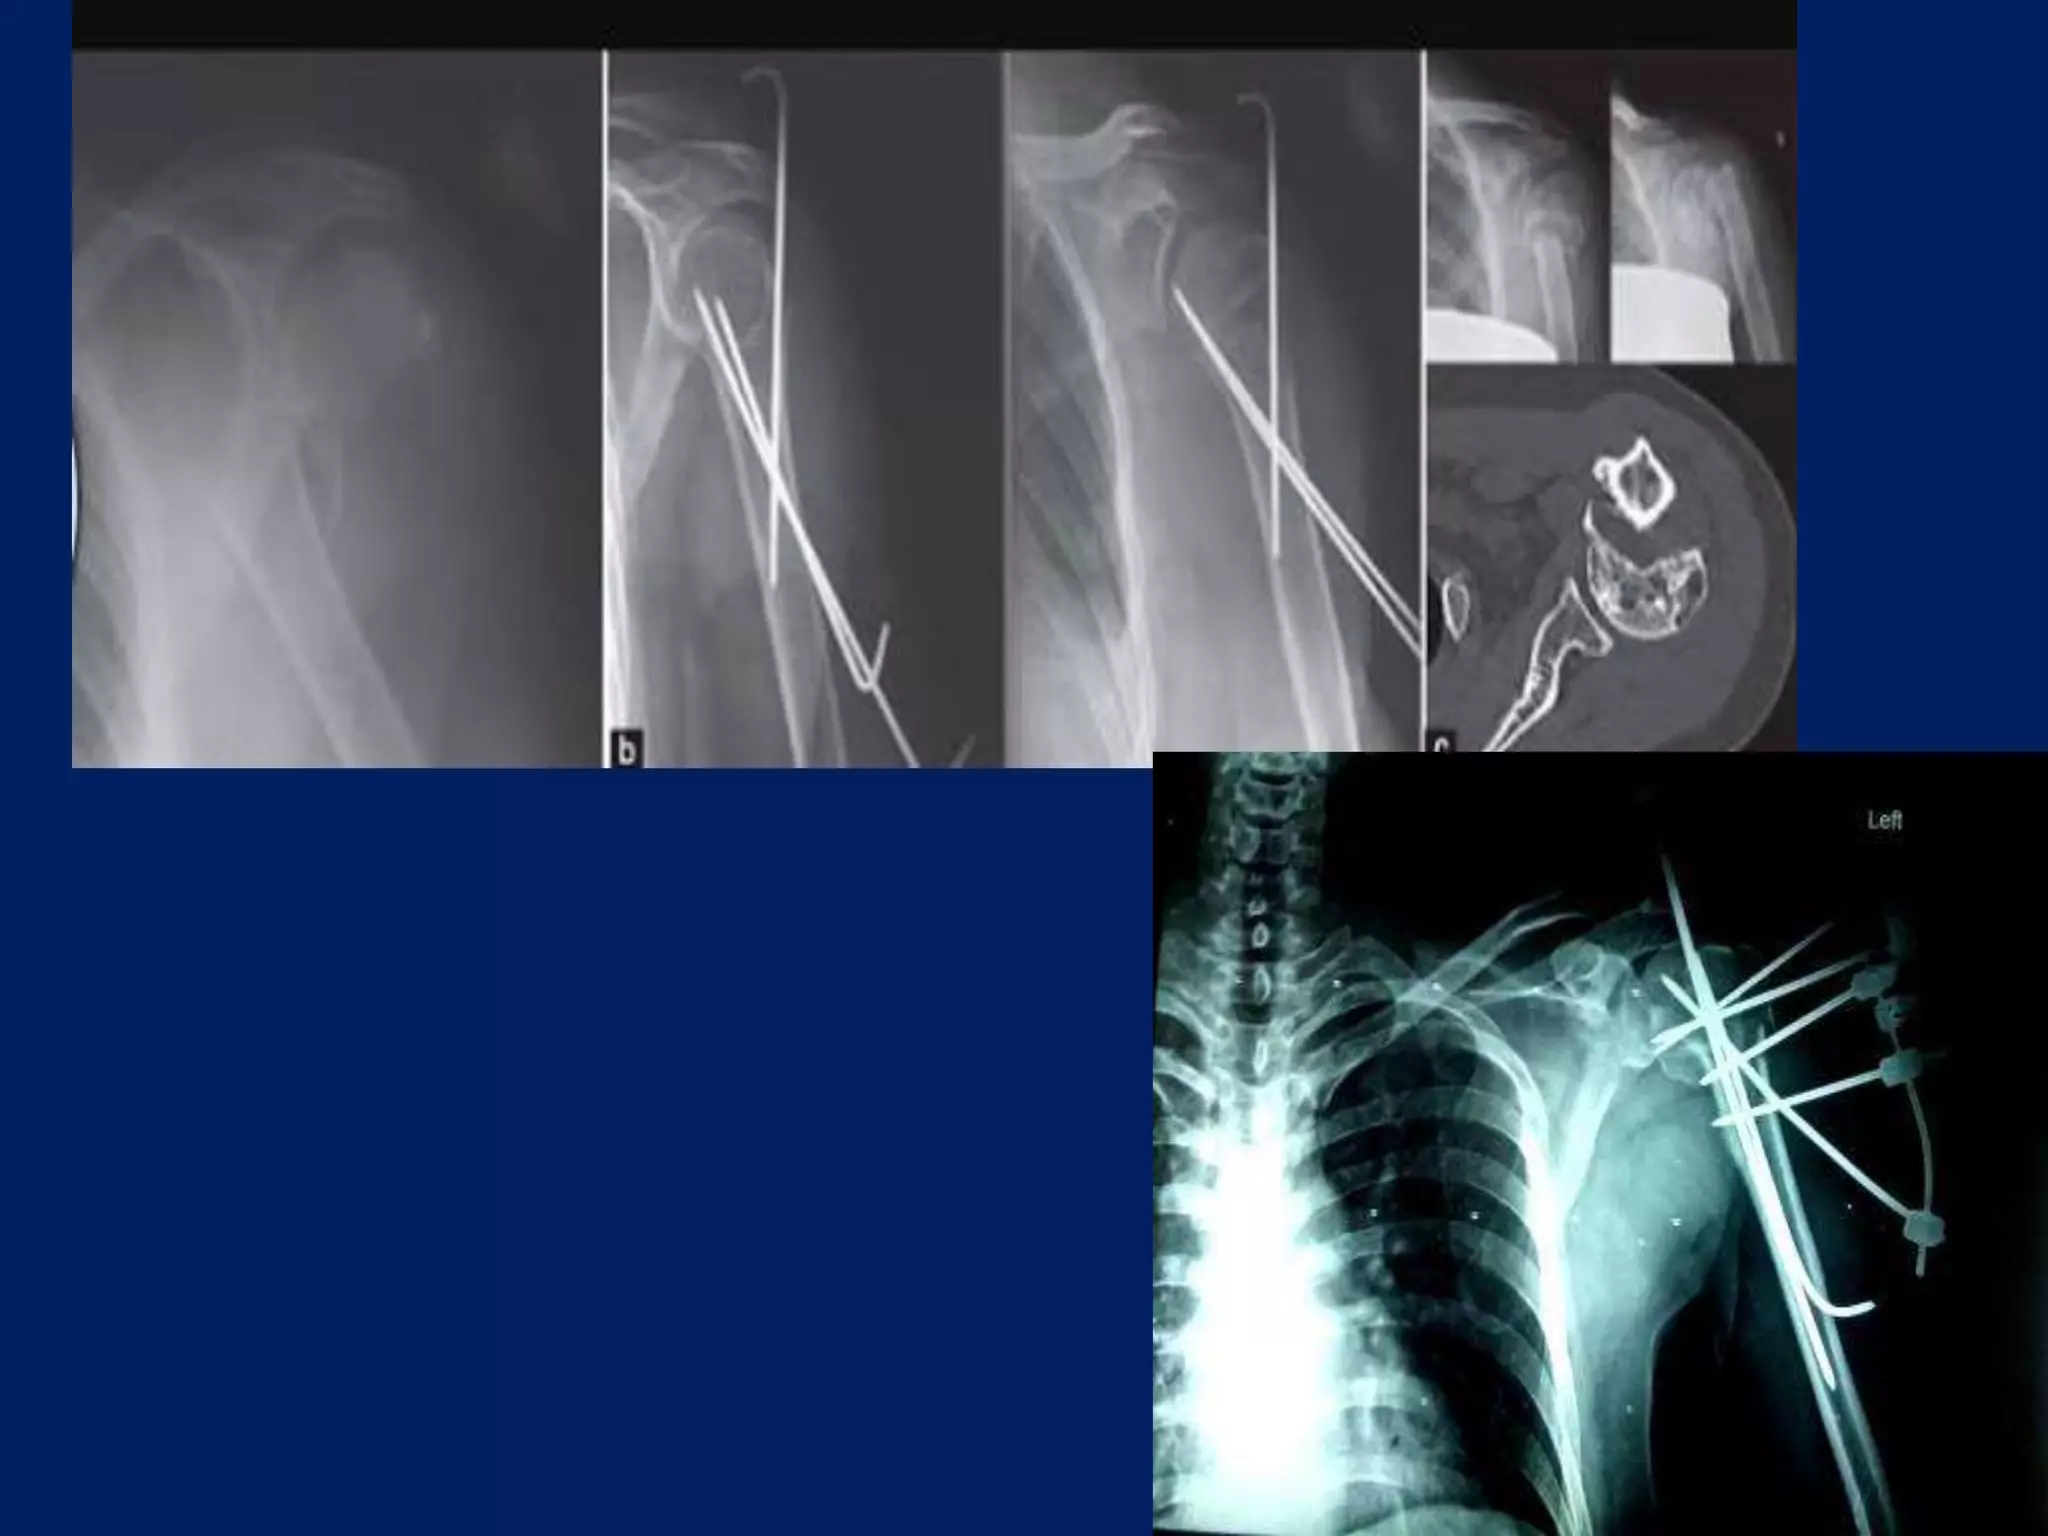

Fracture proximal humerus Fixation with K wires and External fixator

Nabeil Ebraham’s Technique •4 Step technique • 2 pins of 2.5 mm inserted in Shaft. • 2 pins of 2.5 mm in Head. • Head is externally rotated to place Greater tuberosity pin, avoids Axillary nerve, Posterior circumflex humeral artery. • Pins are used as joystick to reduce the fragments external fixator then applied. • Additional anterior pins are added for stability.